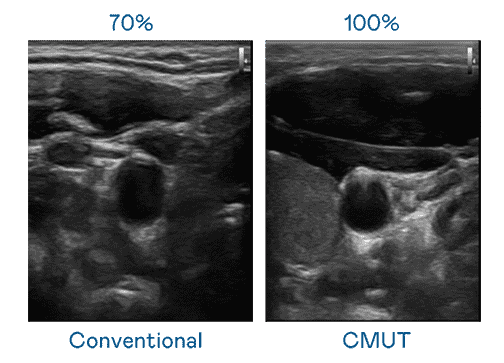

CMUT 技术是一种用电容式微机电元件来产生超音波讯号的技术。。。。与传统 PZT 压电式技术相比,,,CMUT 频宽增加 30%,,,,更宽频的超音波讯号让影像解析度大幅提升,,,,是实现高影像品质医疗超音波扫描、、、、促进精准医疗发展的关键技术。。

大频宽带来超清晰影像

超音波影像的解析度高低,,,首先取决于探头能发出的讯号频宽。。。2468BET CMUT 可提供高清晰的超音波讯号,,提供高频宽、、、高灵敏度、、影像纹理细节更高的超音波影像,,,协助医护人员缩短影像判读时间及利用精准的医疗影像进行诊断。。。。